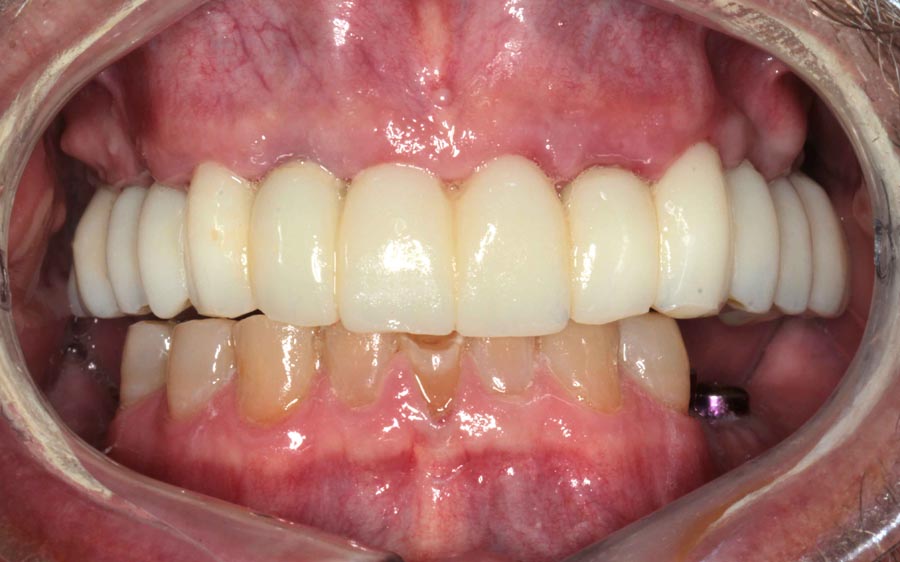

Final prostheses, intraoral, frontal. Homecare is still a problem. The final restorations are much kinder to the tissues and we hope this will resolve some of the inflammation.

Post-treatment panoramic image. This treatment is as good as humans can do in 2025. This patient was undecided whether to keep his teeth. We gave him the chance to consider this option but later he decided to have full mouth implants. We changed gears and were able to deliver World Class outcomes. We continue to encourage better homecare. This patient is from out of state so we haven’t seen his tissues in almost a year.